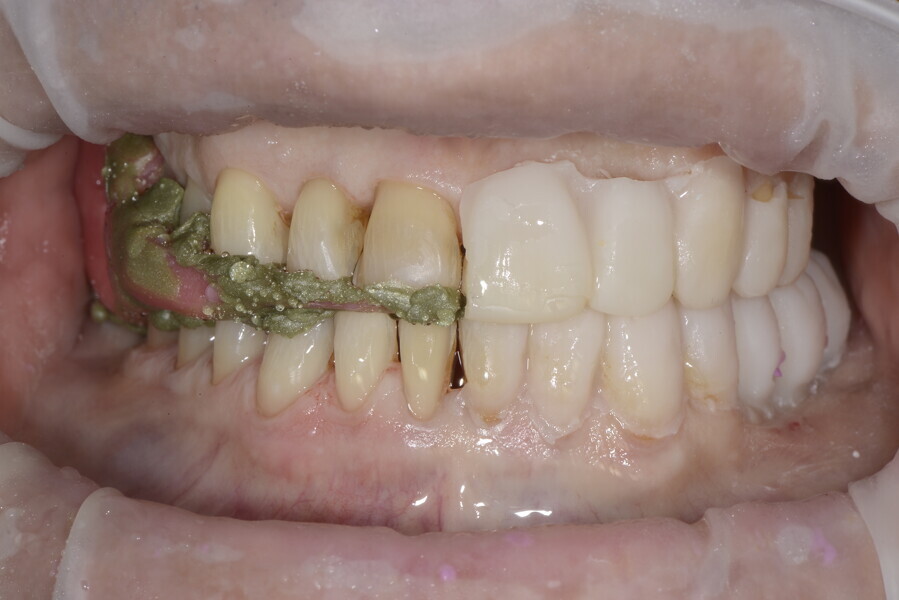

During the first visit, we checked the centric relation with cotton rolls, eliminating the posterior mesialising precontact and then performed a direct composite aesthetic and functional mock-up in this new position, not only to motivate the patient regarding the final result but also to help him understand better overall why tongue therapy, tooth alignment and dental resurfacing for augmentation of the vertical dimension of occlusion were required (Figs. 14 & 15).